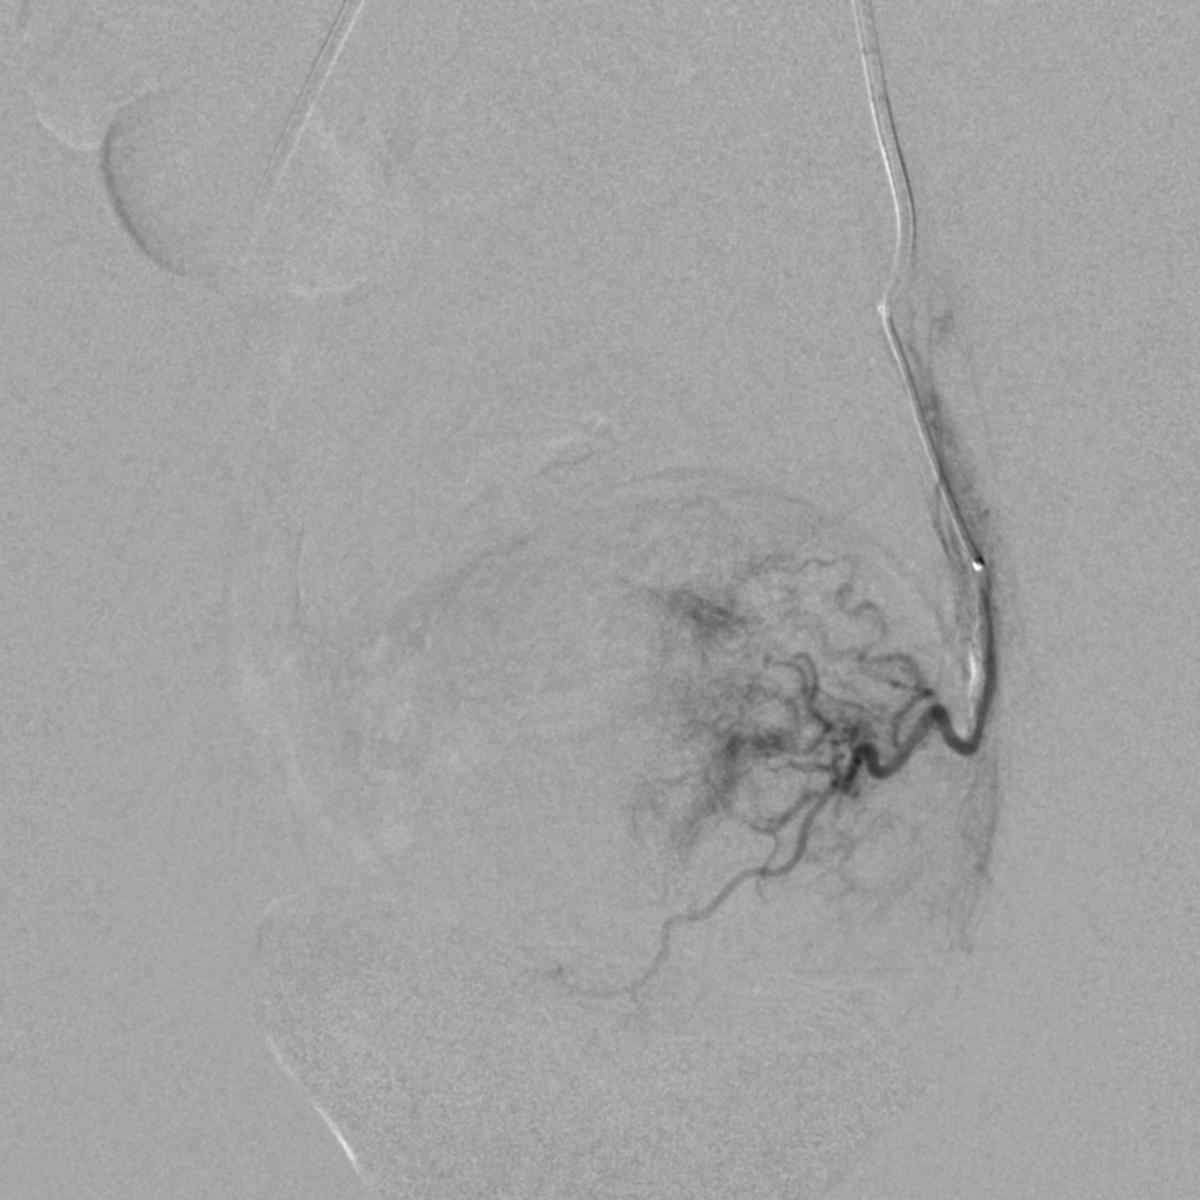

患儿完成入院前术前检查,并进行了全科的术前讨论。结合患儿体征及相关的术前检查,目*考前**虑PROS综合症。目前主要解决的是月经出血的问题,可以通过栓塞双侧子宫动脉来进行治疗。患儿全麻后,使用5F穿刺针行右股动脉穿刺,成功后置入5F血管鞘,导丝引导下置入5F Headhunter Angiopointer造影导管,在导丝引导下选入髂内动脉,进入子宫动脉,造影见左侧子宫动脉远端纤细,右侧子宫动脉螺旋增粗,微导丝引入微导管进入子宫动脉,使用聚乙烯醇颗粒栓塞剂350um-560um,栓塞微粒球(300-500um)分别行双侧子宫动脉栓塞,栓塞后造影未见子宫动脉远端分支显影。

左侧子宫动脉远端纤细